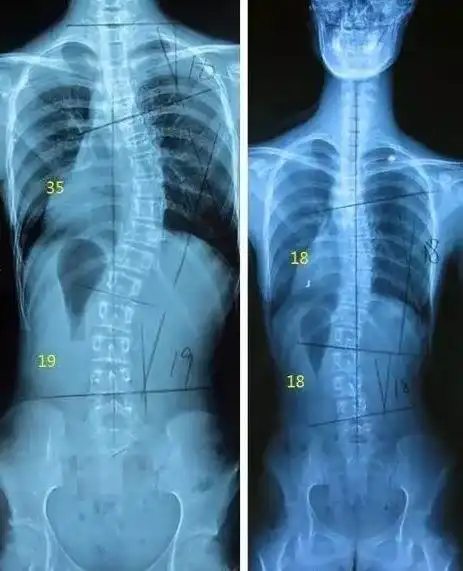

13岁少女肩膀一高一低!专家:当心青少年脊柱侧弯

脊柱侧弯少年的改变